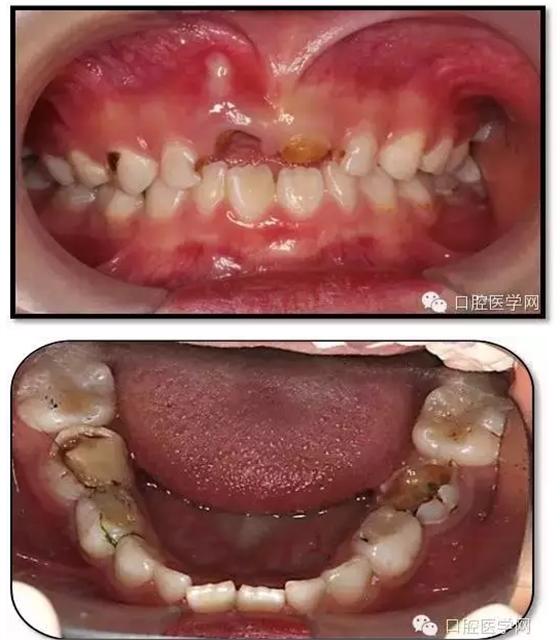

患兒,女,6歲1個(gè)月

主訴:坐下后牙頰側(cè)牙床鼓膿包2周

現(xiàn)病史:左下后牙頰側(cè)牙床鼓膿包2周,左側(cè)進(jìn)食疼痛,來診求治?;純簭?歲開始刷牙,父母幾乎不幫助刷牙。從沒用過牙線,愛吃甜食,偶爾睡前吃甜食。雙側(cè)下后牙1年前在我院兒科行根管治療。

臨床檢查: 75OL齲洞, 舌側(cè)牙體完全劈裂斷端齊齦,探及大量軟化腐質(zhì)。頰側(cè)牙齦紅腫見瘺管,擠壓大量溢膿。叩(±),不松動(dòng)。X線:75根管空虛,牙根吸收約1/2,根尖周及根分歧大面積透射影,35發(fā)育4期,骨硬板尚連續(xù);51殘根,唇側(cè)牙齦瘺管,叩(±),不松動(dòng)。X線:51牙根吸收約1/2,根尖周低密度影。

85O、84DO充填體邊緣不密合,叩(±),不松動(dòng)。84頰側(cè)牙齦略紅腫。X線:84遠(yuǎn)中根及髓室底完全吸收,根分歧透射影,近中根內(nèi)側(cè)見外吸收,44上方骨硬板連續(xù)。85近中根完全吸收,髓室底吸收,根分岐透射影,遠(yuǎn)中根管內(nèi)見根充影像。45發(fā)育4期,骨硬板連續(xù)。

55OL、65OL、74O、53DL齲洞,叩(-),不松動(dòng),齦無異常。

16OL、46OB、26O、36OB窩溝探及淺齲壞,叩(-),不松動(dòng),齦無異常。